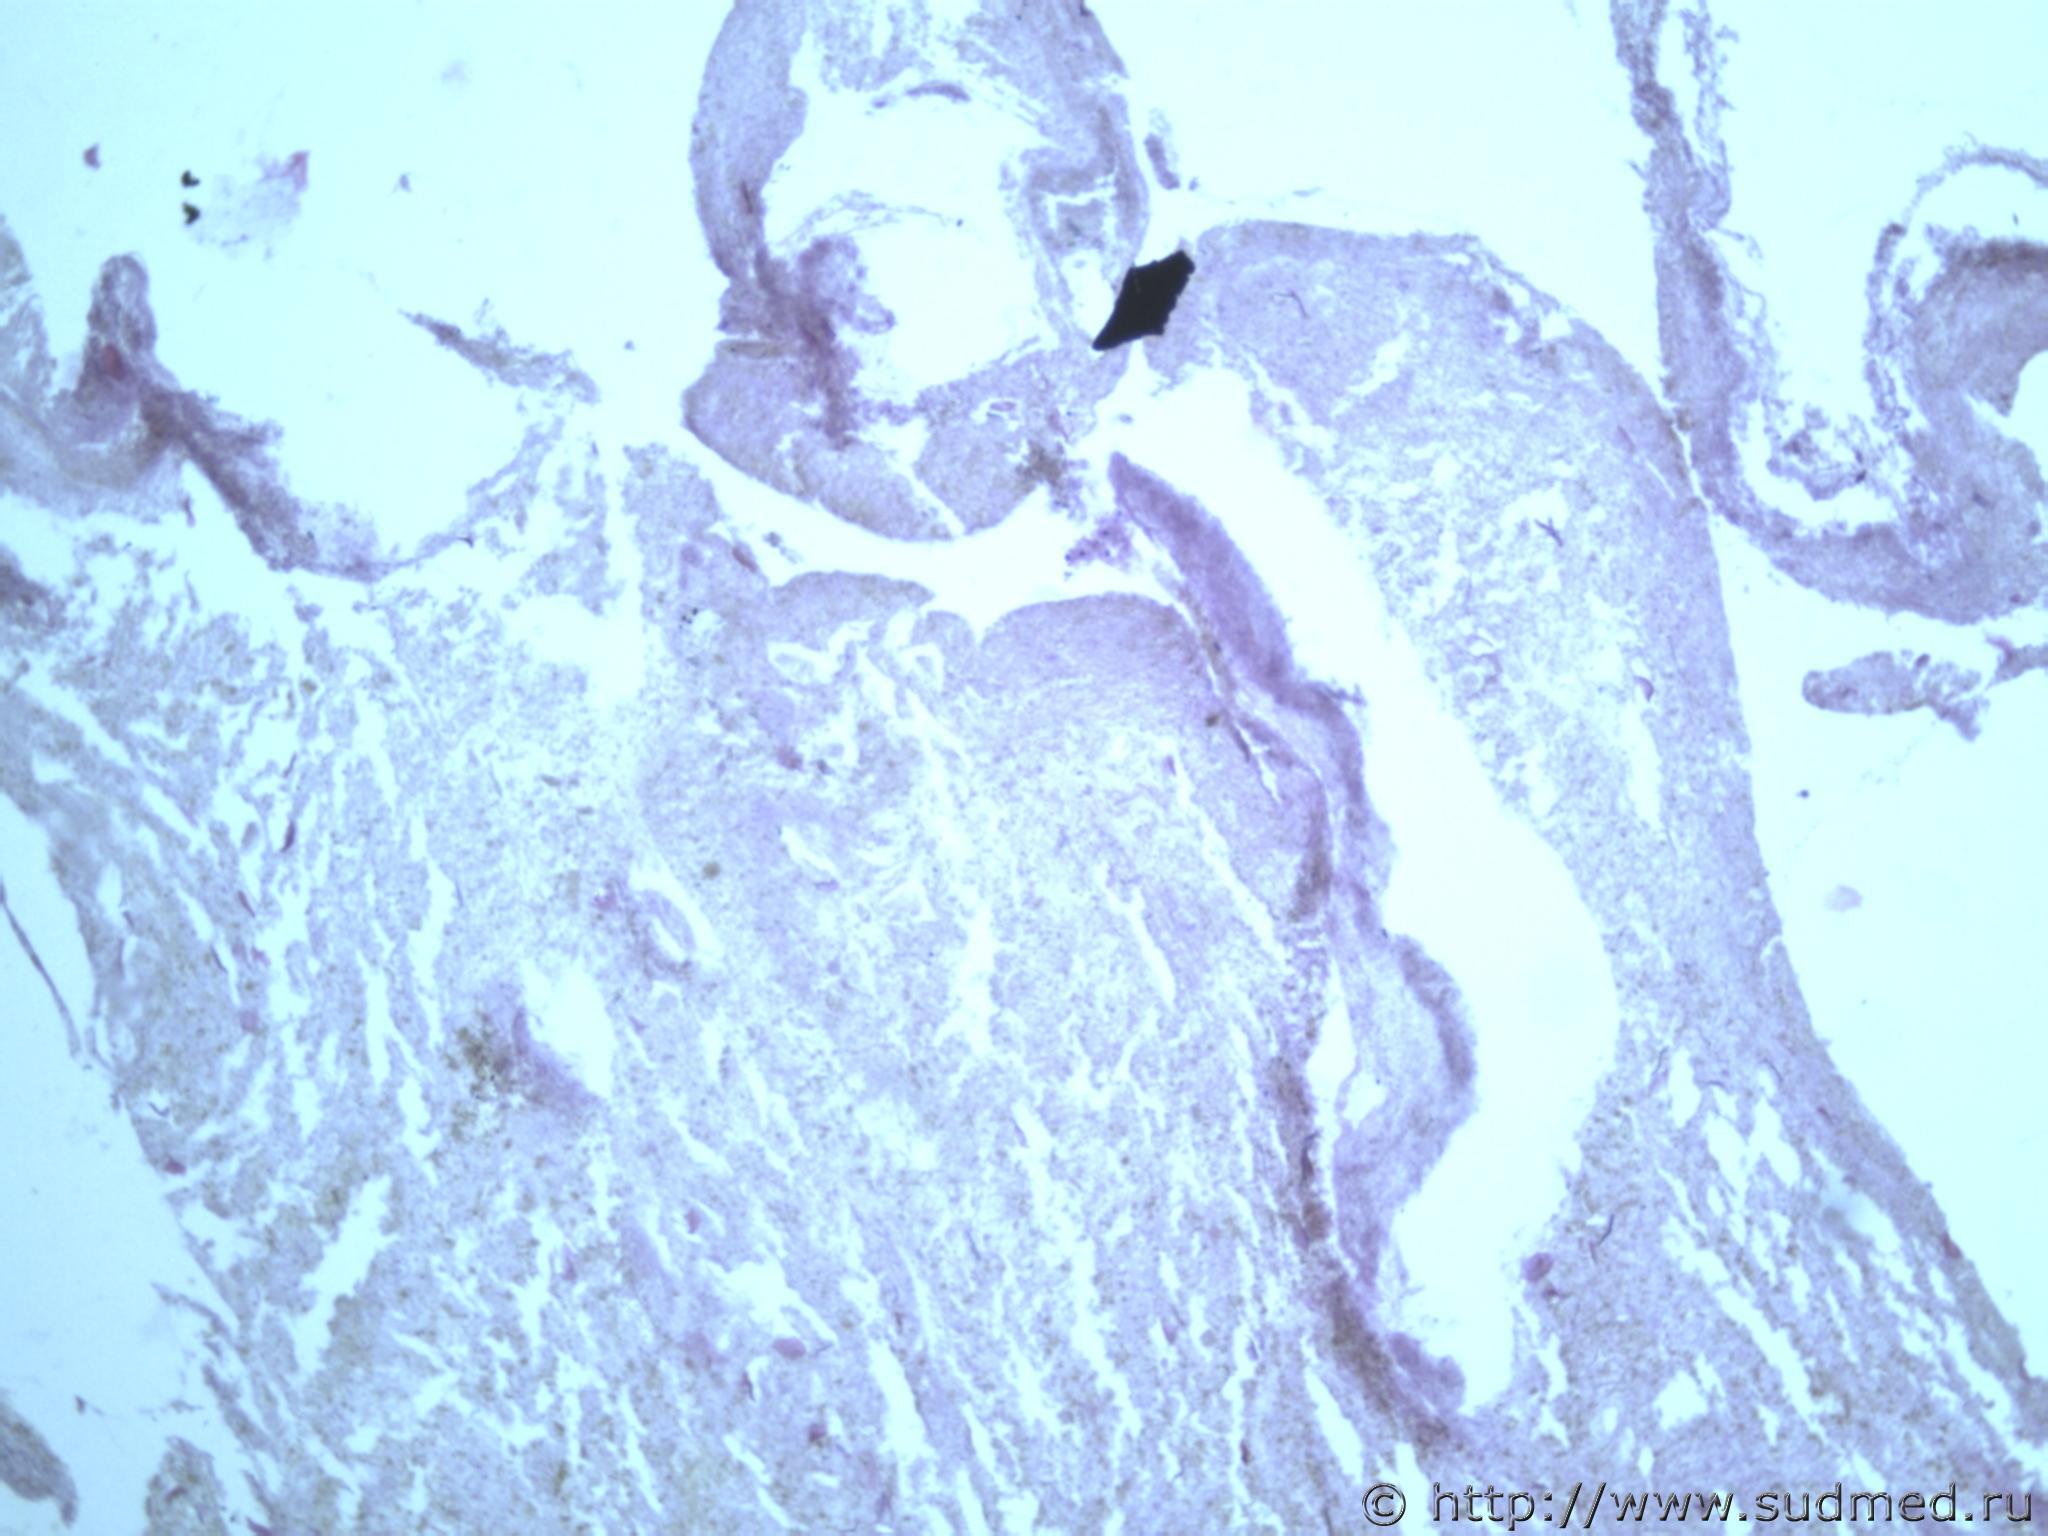

всем здравствуйте. хотела бы знать ваши мнения. провожу экспертизу. препараты как и труп новорожденного гнилые либо в аутолизе страшном. в легком картина такова, что ткань "плотная". просвет различимых альвеол в виде щелей и по всем полям зрения элементы околоплодных вод. одна артерия пуповины спазмирована. остальные сосуды непонятно : просвет их спавшийся но без признаков спазма. они как будто сплющены. да и сама пуповина в виде тонкого тяжа, видно из-за гнилостных изменений. под тмо спинного мозга признаки кровоизлияния, как и в коже с шеи. в коже головы с полнокровием отдельных сосудов. мать утверждает что ребенок после родов не сразу но все же шевелился и кричал. хотя перед этим он выпал у нее из матки на пол, ударившись головой. и со слов матери у него была пена изо рта и он хрипел.

Микрофото лёгких показать можете ?

сегодня сфоткаю конечно. но не факт что будут качественные фотки. плавательная проба - "сомнительная".

Судебная медицина - Прикрепленное изображение Судебная медицина - Прикрепленное изображениеСудебная медицина - Прикрепленное изображениеСудебная медицина - Прикрепленное изображениеСудебная медицина - Прикрепленное изображение

ну вот как то так. там еще и фотки пуповины.

Плохо,материал гнилой.

Остановился бы на дышавшем лёгком.

5 фото в сообщении №4 и 8 фото в сообщении №5 не наводит ли на мысль о дышавшем лёгком ?

Про остальные фото молчу,там или ничего не видно или же есть оптически пустые пузыри,что вероятнее всего,проявления гниения.